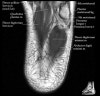

- Axial section

Axial PD fat suppression evaluates the tendons and ligaments of the ankle particularly after acute/subacute injuries. It also is sensitive to talar dome osteochondral defects. Alternatively, a T2 sequence can be used to eliminate magic angle artifact that may occur as the tendons travel around the malleolar turns.

Tibiofibular ligaments

Lateral ankle ligaments

Deltoid and spling ligaments

Tendon(Achilles, Medial, Lateral, Anterior)